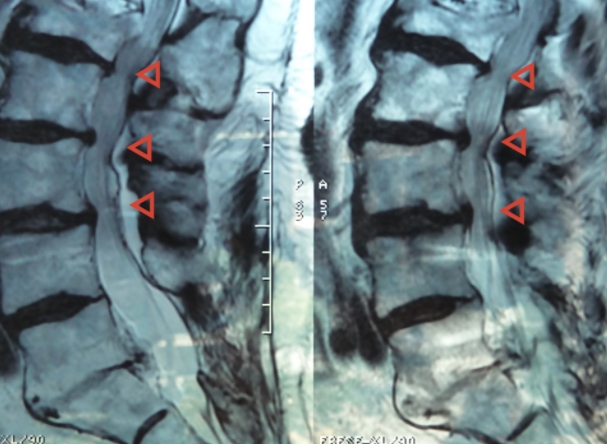

척추는 추골이라 불리는 뼈가 연결되어 이루어져 있습니다. 그런데 나이를 먹으면서 노화와 함께 추골에 있는 척추관이라 불리는 신경이 통과하는 길이 좁아지게 됩니다. 이렇게 좁아지게 되면 그 안을 통과하고 있는 신경이 압박을 받아서 허리통증과 엉덩이, 다리가 저리는 증상 까지도 나타나게 됩니다.

노화 등의 영향으로 추간판이나 요추가 변형 변성되어 척추관이 좁아지면 그 안을 통과하는 마미신경이 압박을 받게 됩니다. 마미신경이란 다리쪽 신경을 조절하는 신경입니다. 그런데 이 부분이 압박을 받으면 신경이 영향을 받아 다리에까지 통증이 나타나고 저리는 등의 척추관 협착증 증상 보이게 됩니다.

척추관 협착증 이란 노화로 인한 변화로 추간판 변성과 뼈 변형, 인대가 늘어나는 등의 여러가지 증상의 원인이 되기도 합니다. 하지만 이런 협착증 증상 이라는 것이 하지의 혈전성 정맥류, 동맥경화증 등 혈류장애질환의 증상과도 비슷하기 때문에 정확한 진단을 받아야 합니다. 허리 디스크와의 차이는 잘 걸리는 연령대로 먼저 추측을 해 볼 수는 있습니다.

그리고 척추관 협착증 으로 인한 허리통증 자체는 허리 디스크의 통증에 비교하면 그렇게 심하다고는 할 수 없습니다. 하지만 등을 쭉 펴고 서거나 걷거나 하는 등의 척추관이 좁아지는 자세를 취하면 마미신경이 더 압박을 받아 하지가 저리고 다리 움직임이 나빠지게 됩니다.